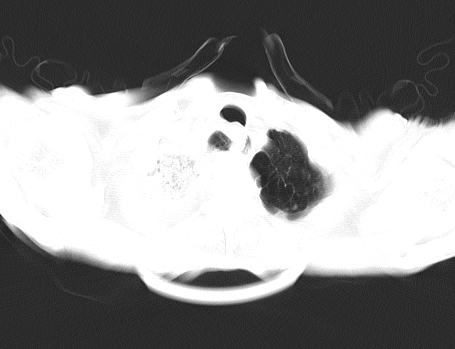

以下是引用gaoshengjiang在2008-5-30 19:53:00的发言:[br]右上叶可见大片实变影,其内可见充气支气管影及囊状影,右上叶尖端支气管走形区可见结节样影,左侧胸腔内可见胸腔胃影。纵隔淋巴结肿大。[br]考虑:1.右上肺阻塞性肺炎伴肺脓肿形成。支持转移所致。[br] 2.左侧胸腔胃。